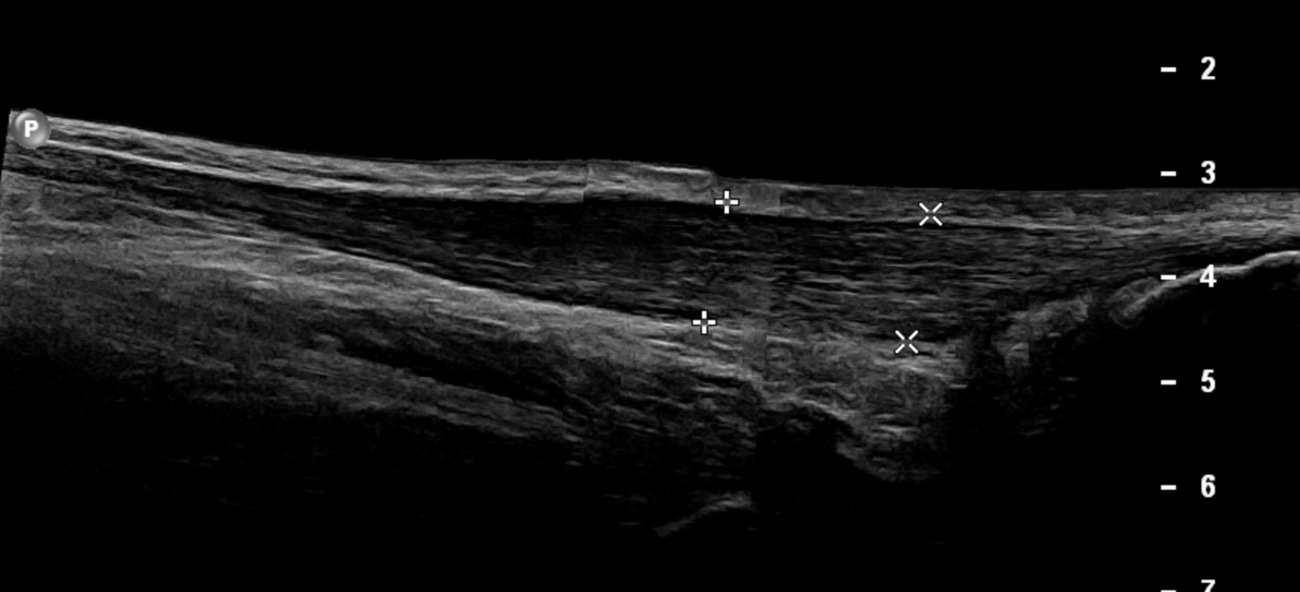

panoramic view of Achilles tendinosis

Important swelling of the left Achilles tendon is noted without evidence of intrasubstance tear in keeping with tendinosis. Excessive, hypervascular peritendinitis is also noted. The retrocalcaneal bursa shows wall thickening and isoechogenic fluid content without hypervascularity in keeping with chronic bursitis.